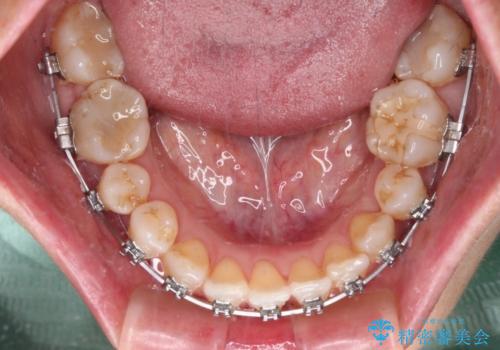

- メタルブラケット

- 1年8ヶ月

- 10-30回

奥歯の噛みにくさが顕著なためマウスピースではなく、ワイヤー装置による矯正治療を行うこととしました。

下顎の正中を歯1本分ずらした位置とすることで、外見上の骨格的なずれをカバーするように計画しました。

クロスバイトを改善したことで、前歯の負担が軽減し、安定して噛めるようになりました。